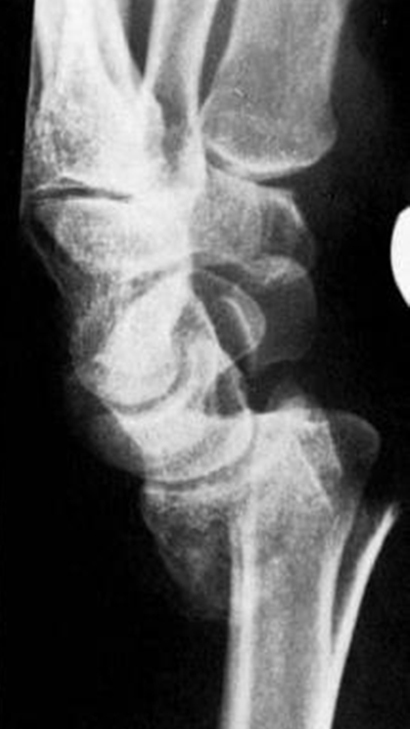

柯氏骨折图片,

钩状骨裂缝骨折

柯莱氏骨折

大多数柯氏骨折采用轻石膏或夹板固定处理.